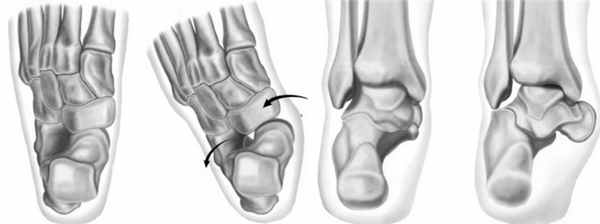

Далее происходит последовательная дегенерация структур поддерживающих продольный свод стопы – переднемедиальной пяточно-ладьевидной связки, подошвенной фасции, подошвенных связок. Происходит подошвенно-внутренняя миграция головки таранной кости, с уплощением продольного свода стопы. В более поздних стадиях возникает ригидная костная деформация.

Классификация недостаточности сухожилия задней большеберцовой мышцы.

Деформация

Данные осмотра

Данные рентгенографии

Деформация отсутствует. Теносиновит.

Может встать на мыске одной ноги

Норма

Динамическое плоскостопие заднего отдела стопы, нормальный передний отдел стопы.

При вставании на мыске одной ноги появляется лёгкая подтаранная боль

Коллапс продольного свода стопы

Динамическое плоскостопие заднего отдела стопы, отведение переднего отдела стопа ( симптом «слишком много пальцев», >40% дефекта покрытия ладьевидной костью суставной поверхности таранной кости)

Коллапс продольного свода стопы.

Ригидное плоскостопие. Ригидное отведение переднего отдела стопы.

Ригидная вальгусная деформация заднего отдела стопы.

При вставании на мыске одной ноги появляется выраженая подтаранная боль

Коллапс продольного свода стопы, подтаранный артрит.

Ригидная вальгусная деформация заднего отдела стопы. Компрометация дельтовидной связки.

При вставании на мыске одной ноги появляется выраженая подтаранная боль, боль в голеностопном суставе.

Хронический подвывих в голеностопном суставе.